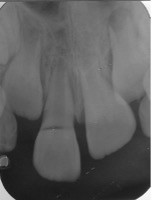

Se presenta el caso de un paciente de sexo femenino, de 8 años de edad. La paciente acudió acompañada con su padre al servicio de endodoncia del Instituto Nacional de Salud del Niño en Lima- Perú, con antecedentes de traumatismo dental, en sector antero superior y con dolor espontáneo. Al examen clínico intraoral, se evaluó que el diente 11 presentaba una ligera movilidad dental y al examen radiográfico se observó diente 11 no vital, ligero ensanchamiento del ligamento periodontal y desarrollo radicular en estadio 8 de Nolla (Figura 1 y 2). Se evaluó el caso y se realizó la explicación de las ventajas y desventajas del tratamiento de revascularización pulpar al padre de familia y se procedió a la firma del consentimiento informado para el tratamiento.

Figura 2: Radiografía periapical de diagnóstico.